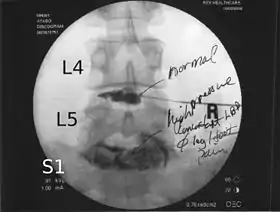

Lumbar provocative discography showing a degenerated disc, L5-S1 with normal disc L4-L5

Needles are inserted through the back into the disc near the suspect area, guided by fluoroscopic imaging. Fluid is then injected to pressurize the disc, and any pain responses are recorded.